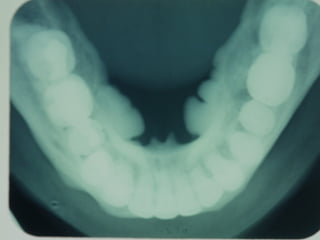

Torus

• Paltino